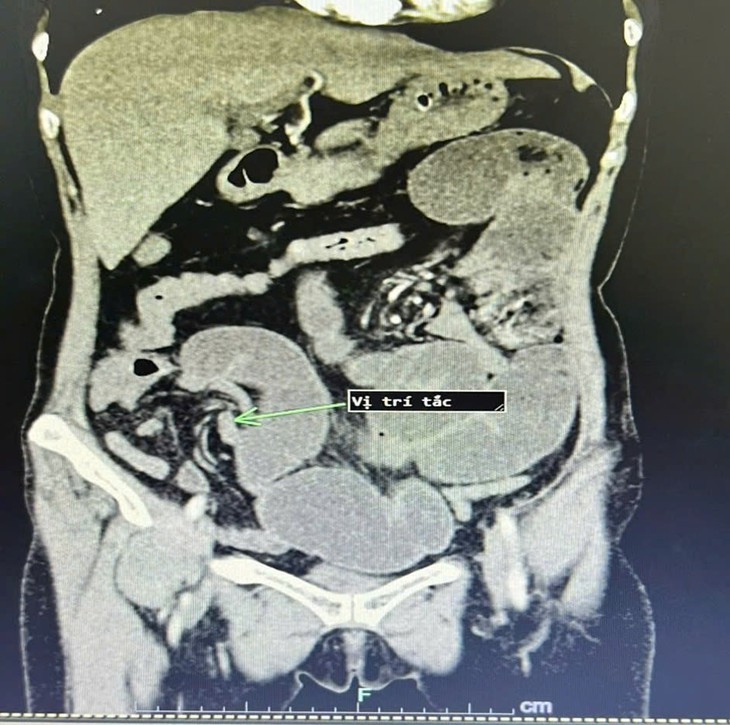

| Hình ảnh chụp cắt lớp vi tính sau khi phẫu thuật của người bệnh, tình trạng tắc ruột đã cải thiện rõ rệt. Ảnh BVCC |

Trong mổ các BS nhận thấy các quai ruột non giãn to, dính gập góc gây tắc hoàn toàn đoạn hồi tràng gần góc hồi manh tràng. Các Bs đã tiến hành gỡ dính, cắt đoạn ruột tắc lập lại lưu thông ruột. Hiện tại, người bệnh đã ổn định và được ra viện.